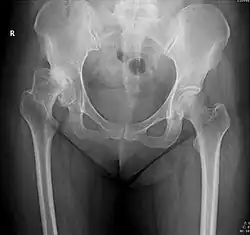

Projectional radiography ("X-ray") is the first imaging technique of choice in hip pain, not only in older people with suspected osteoarthritis but also in young people without any such suspicion. In this case plain radiography allows categorization as normal hip or dysplastic hip, or with impingement signs, pincer, cam, or a combination of both.[1]

X-Ray

Projectional radiography ("X-ray") is currently useful not only in older people in whom osteoarthritis of the hip is suspected but also in younger people without osteoarthritis, who are being evaluated for femoroacetabular impingement (FAI) or hip dysplasia.[1]

Plain radiography allows us to categorize the hip as normal or dysplastic or with impingement signs (pincer, cam, or a combination of both). Besides these, pathologic processes like osteoarthritis, inflammatory diseases, infection, or tumors can also be identified (Figure 1).[1]